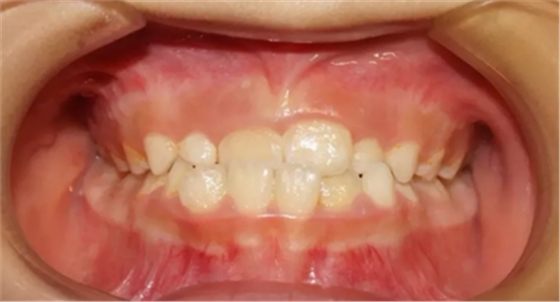

02 下頜后縮

因“沒有下巴”“臉型短”前來就診,該如何避免?